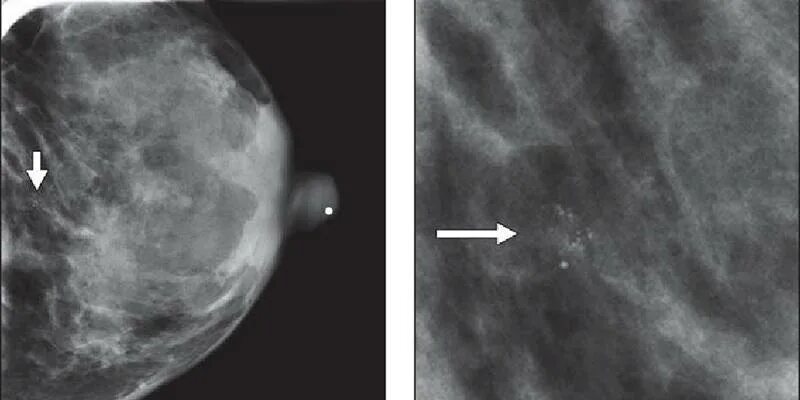

Протоковый «рак на месте». внутрипротоковая карцинома узи. инфильтративная опухоль молочной железы. протоковая карцинома молочной железы g3.

Очаговое образование молочной железы фиброаденома. объемное образование в молочной железе. узловое образование молочной железы. неоплазия молочной железы.

Узловая форма фиброзно-кистозной мастопатии на узи. малигнизация фиброаденомы молочной железы. узловая форма мастопатии молочной железы. узловая мастопатия на узи молочной железы.